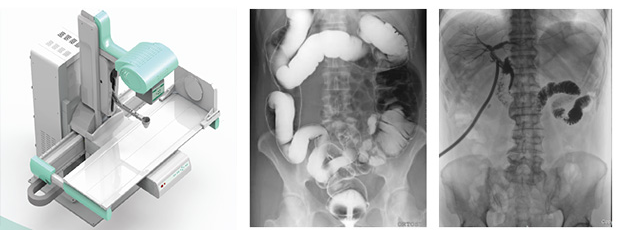

只需一块动态平板探测器,即可高效轻松实现摄影、透视和造影功能,几乎可以满足医院全科室的临床检查需求。

1)大视野无遗漏

17*17英寸的高清像素动态平板探测器,能对胸部、腹部等部位实现大范围全覆盖,动静态之间无感切换。透视检查无须对患者重新定位便可观察到足够大的人体器官组织,避免漏诊误诊。更好地减少了曝光时间,也减少了病人的辐射剂量。

大尺寸动态平板技术,覆盖检查面积范围广,轻松实现胃十二指肠等大面积造影,无需移动即可观看整个动态过程,避免噪点对图像的影响。

2)图像质量无畸变,无失真

高效动态平板技术,图像不会有几何畸变,提供高分辨率和精确的图像,为临床诊断提供精准依据。